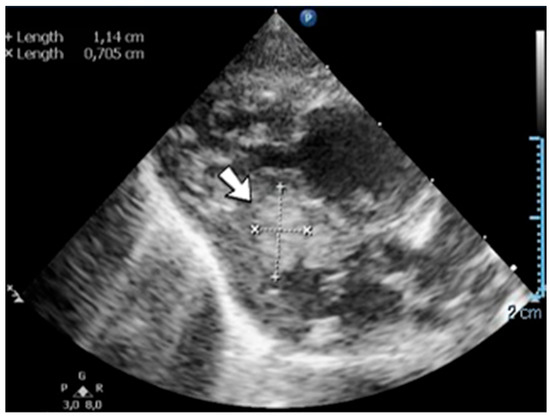

A 19-day-old male neonate (35–36 weeks, 2.20 kg) presented with thrombosis of the right pulmonary artery diagnosed on the same day at another pediatric emergency department, where treatment with continuous heparin infusion was initiated. The admission laboratory findings showed elevated c-reactive protein, modified coagulation tests (ongoing anticoagulation treatment), and elevated D-dimer tests. The cardiac ultrasound identified thrombi in the right atrium and ventricle (Figure 15). Therapy with heparin was continued, to which alteplase was added. After four days of anticoagulation and fibrinolytic therapy, the thrombi could no longer be noticed on ultrasound or CT scan.

Figure 15.

Intracardiac thrombosis was identified on cardiac ultrasound: in the right pulmonary artery (A), the right atrium (B), and the right ventricle (C).

Genetic testing confirmed inherited thrombophilia, with a positive MTHFR C677T homozygous gene mutation and Antithrombin, Protein S, and Protein C deficiencies. A mild elevation of PAI-1 levels was detected. There was limited information about the family history.